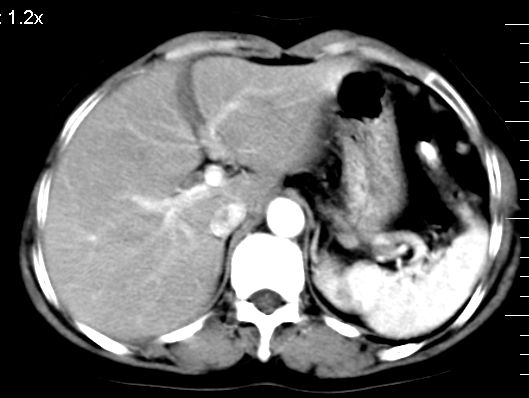

肝大小形态未见异常,肝内外胆管无扩张,肝s8段见一动脉期明显血管样强化结节,门脉期呈高密度,延迟期呈等密度,胆囊不大,增强扫描见胆囊及胆囊颈管壁增厚,有强化。

2、肝s8段结节,考虑小血管瘤。

肝右上叶血管瘤!

考虑肝右叶前上段包膜下小血管瘤。

考虑肝右叶前上段包膜下小血管瘤

支持肝右前叶上段小血管瘤

支持;右肝8段小血管瘤,左肾囊肿.